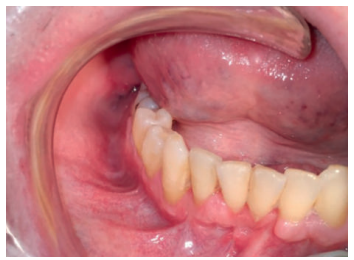

A los 7 días se revisó la herida quirúrgica, mientras que la retirada de puntos se realizó a los 15 días. Al mes se había producido una buena cicatrización de la zona intervenida y aunque el paciente no refirió molestias, si indicó una sensación de parestesia en el labio inferior derecho. (Figuras 12 y 13).